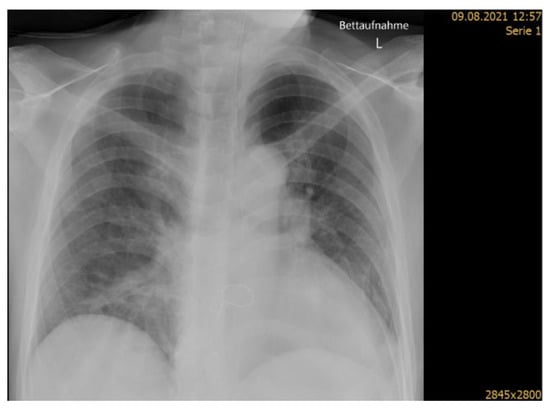

Seven days post stroke onset, the patient was moved to a general medical ward, where he was treated for a further two weeks. Ten days post stroke, fever, worsening cough and dyspnea raised the suspicion of pneumonia. Subsequent chest X-ray imaging (Figure 2) showed incipient right-sided infiltrations in the lungs and ventilation disturbance in the left subfield with a washed-out lateral recess. A diagnosis of hospital acquired pneumonia with suspected aspiration was made in accordance with the Pneumonia in Stroke Consensus Group recommendations [], based on symptoms of fever, worsening cough and dyspnea, crackles on auscultation, raised C-reactive protein (CRP) of 97.4, and new infiltrations on chest X-ray. A 7-day course of treatment with co-amoxicillin (2 g twice daily) was completed with good response, as seen in the CRP decrease to 24 after 4 days.

Figure 2.

Chest X-ray showing signs of hospital acquired pneumonia (right middle lobe pneumonia).